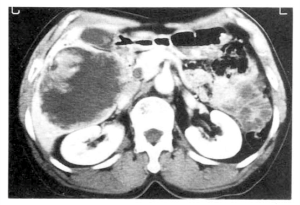

Em geral, a ultrassonografia ajuda, mas a tomografia computadorizada (TC) e a ressonância magnética (RM) do fígado são mais precisas na detecção do câncer.

No fígado, as lesões tendem a ser maiores e múltiplas. Muitas vezes os sintomas iniciais podem ser os mesmos de uma cirrose hepática severa.